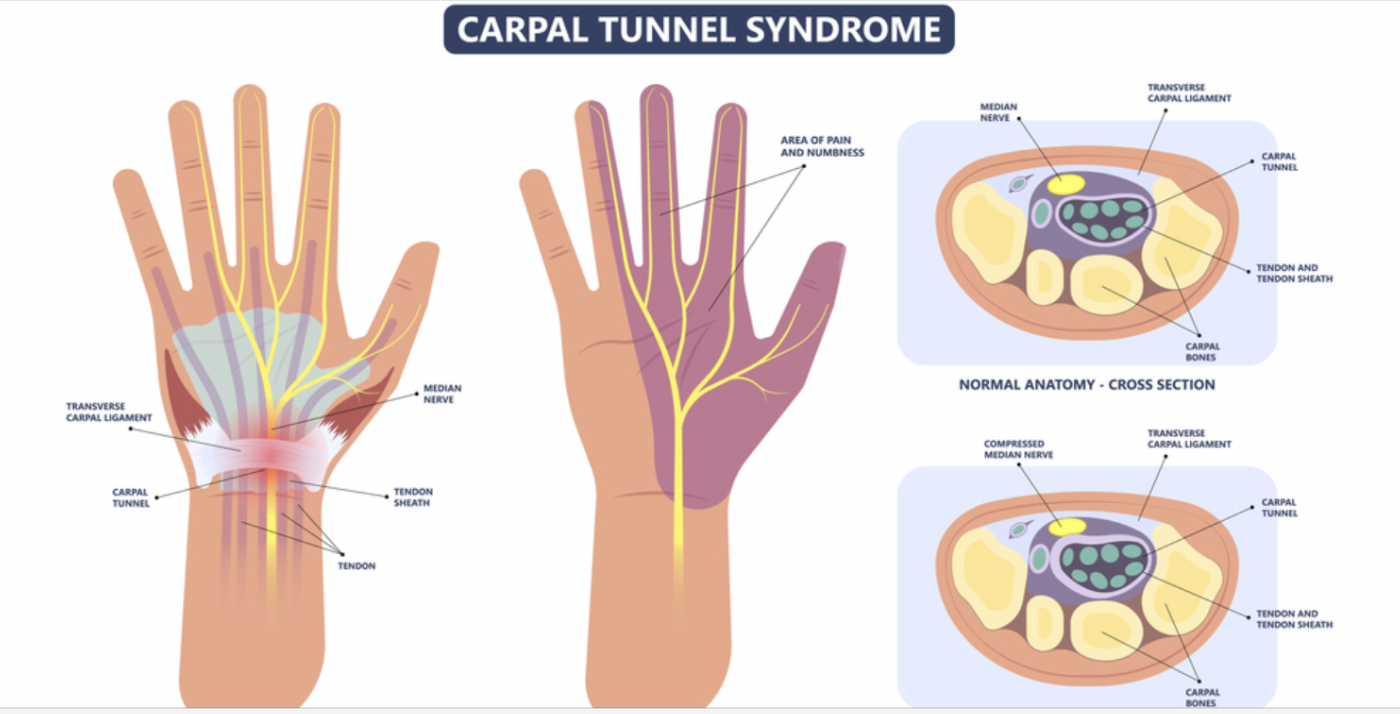

Carpal Tunnel Syndrome Treatment: Surgical vs. Hand Therapy Outcomes

Carpal Tunnel Syndrome Treatment: Surgical vs. Non-Surgical Outcomes Verdugo, R. J., Salinas, R. S., Castillo, J. L., & Cea, J. G. (2008). Surgical versus non-surgical treatment for carpal tunnel syndrome. ...

Carpal Tunnel Syndrome Treatment: Surgical vs. Hand Therapy Outcomes

Carpal Tunnel Syndrome Treatment: Surgical vs. Non-Surgical Outcomes Verdugo, R. J., Salinas, R. S., Castillo, J. L., & Cea, J. G. (2008). Surgical versus non-surgical ...

腕管松解术对双重挤压综合征和颈神经根病患者仍然有效

Hansen, LM, Jiang, EX, Hodson, NM, Livingston, N., Kazanjian, A., Wu, M., & Day, CS(2024)。有无双重挤压的患者...

手法治疗与手术治疗腕管综合症的有效性

Fernández-de-las-Peñas, C.、Cleland, J.、Palacios-Ceña, M.、Fuensalida-Novo, S.、Pareja, JA 和 Alonso-Blanco, C. (2017)。腕管手法治疗与手术治疗的有效性...

腕管综合症:传统手部疗法与神经动力学疗法相比如何?

Hamzeh, H.、Mohammad, M.、Alghwiri, A. 和 Hawamdeh, Z. (2021)。神经动力学与运动疗法对患有以下疾病的人的疼痛和功能的长期影响......